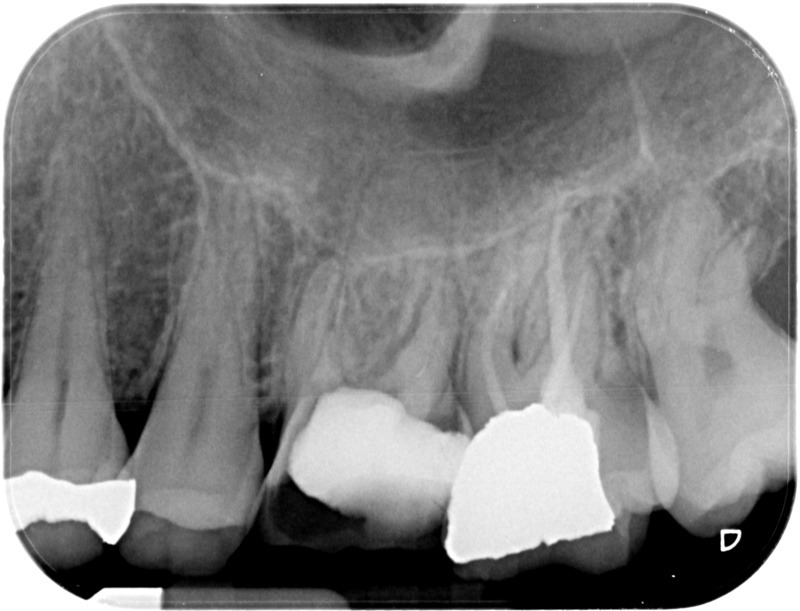

Après

• Traitement endodontique : Sous anesthésie locale et à travers la protection d’un champ opératoire nous accédons à la pulpe de la dent à soigner, puis aux canaux de ses racines que nous devons désinfecter. Ce soin nécessite l’élimination complète de la source de contamination (souvent la carie) parfois sous une ancienne reconstitution ou une couronne qu’il faut alors retirer. Une fois le nettoyage et la mise en forme des canaux réalisés, nous les obturons de façon hermétique avec un ciment et un matériau thermoplastique appelé Gutta Percha. Ceci afin d’empêcher une nouvelle prolifération bactérienne et d’assurer le maintien de la dent dans ses structures de soutien (ligament parodontal et os alvéolaire). L’ouverture effectuée au centre de la dent sera d’abord refermée avec un pansement provisoire avant d’envisager ensemble la reconstitution d’usage : un composite, un inlay-onlay ou une couronne.